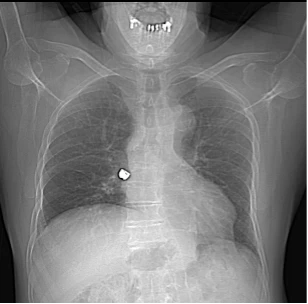

Le CT-scan thoracique, dont on voit ici le scout, met en évidence une structure hyperdense, de densité métallique, au sein de la bronche intermédiaire droite, pouvant correspondre à une couronne dentaire métallique, sans signe d’occlusion complète de la bronche. L’évolution est favorable après récupération de la dent logée dans la bronche intermédiaire droite par bronchoscopie.